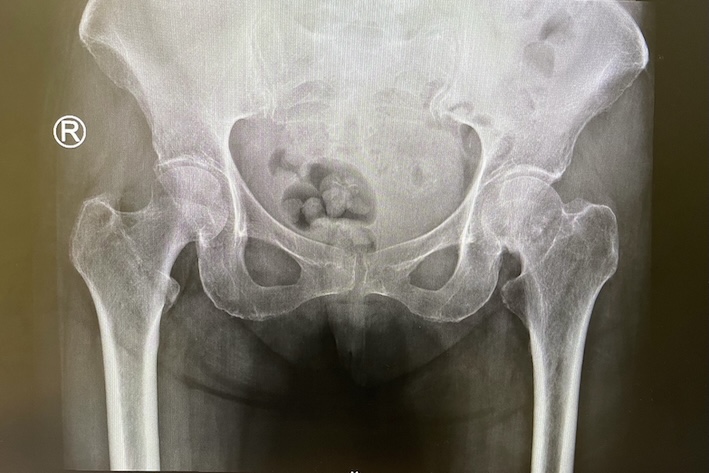

รูปกระดูกสะโพกก่อนผ่าตัด

รอยหักบริเวณสะโพกส่วนใหญ่จะเกิดที่บริเวณคอสะโพก ( Femoral neck fracture) หรือต่ำลงมาบริเวณ แนวรอยต่อระหว่างคอสะโพกและกระดูกต้นขา ( Intertrochanteric fracture)

ผู้ป่วยที่ล้ม ไม่สามารถลุกยืนได้ และมีอาการปวดสะโพกมาก สงสัยว่าจะมีภาวะกระดูกสะโพกหัก ควรได้รับการตรวจ วินิจฉัยที่โรงพยาบาล แพทย์จะทำการ เอ็กซเรย์ข้อสะโพก และในบางกรณี อาจต้องทำ เอ็กซเรย์คอมพิวเตอร์ ( CT SCAN) หรือใช้เครื่องตรวจคลื่นแม่เหล็กไฟฟ้า (MRI) ในกรณีที่มีอาการแสดงของข้อสะโพกหัก แต่ภาพเอ็กซเรย์ ไม่เห็นรอยหักชัดเจน